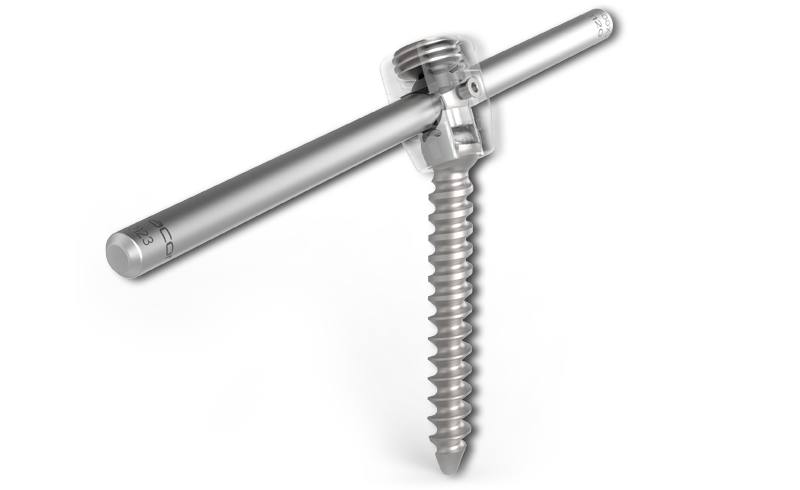

KINERAPatentiertes Design

KINERA ist ein einzigartiges System auf dem Markt. Die Besonderheit liegt am Design des Schraubenkopfes. Medio-Lateral ist der Kopf schwenkbar. Kranio-Kaudal ist der Kopf fixiert. Durch den Einsatz einer Wippe im Schraubenkopf, welche sowohl den Stab von der unteren, als auch von der oberen Seite umschließt, wird die notwendige Flexibilität auch in Kranio-Kaudaler Ebene gewährleistet.

zurückKINERAOffene Fixation

KINERA bietet nicht nur ein einzigartiges Schraubendesign, sondern auch die notwendigen Instrumente, die für degenerative Fälle, Deformitäten oder Trauma vielfältig einsetzbar sind. Besondere Aufmerksamkeit wurde bei der Zusammenstellung des Systems auf eine Reduktion der Instrumententrays gelegt. Alle Operationenmethoden können mit nur zwei Instrumententrays abgedeckt werden.